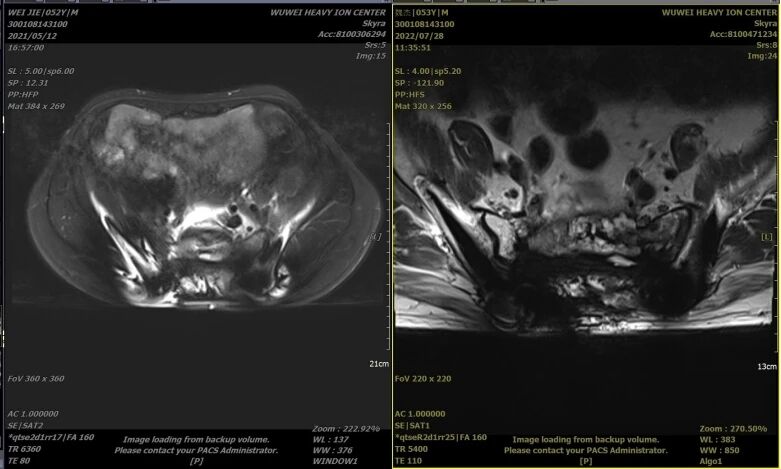

一、患者男,52岁,骶尾部脊索瘤术后复发,2021年5月17日行重离子治疗。

治疗前2021年5月12日 治疗后2022年7月28日